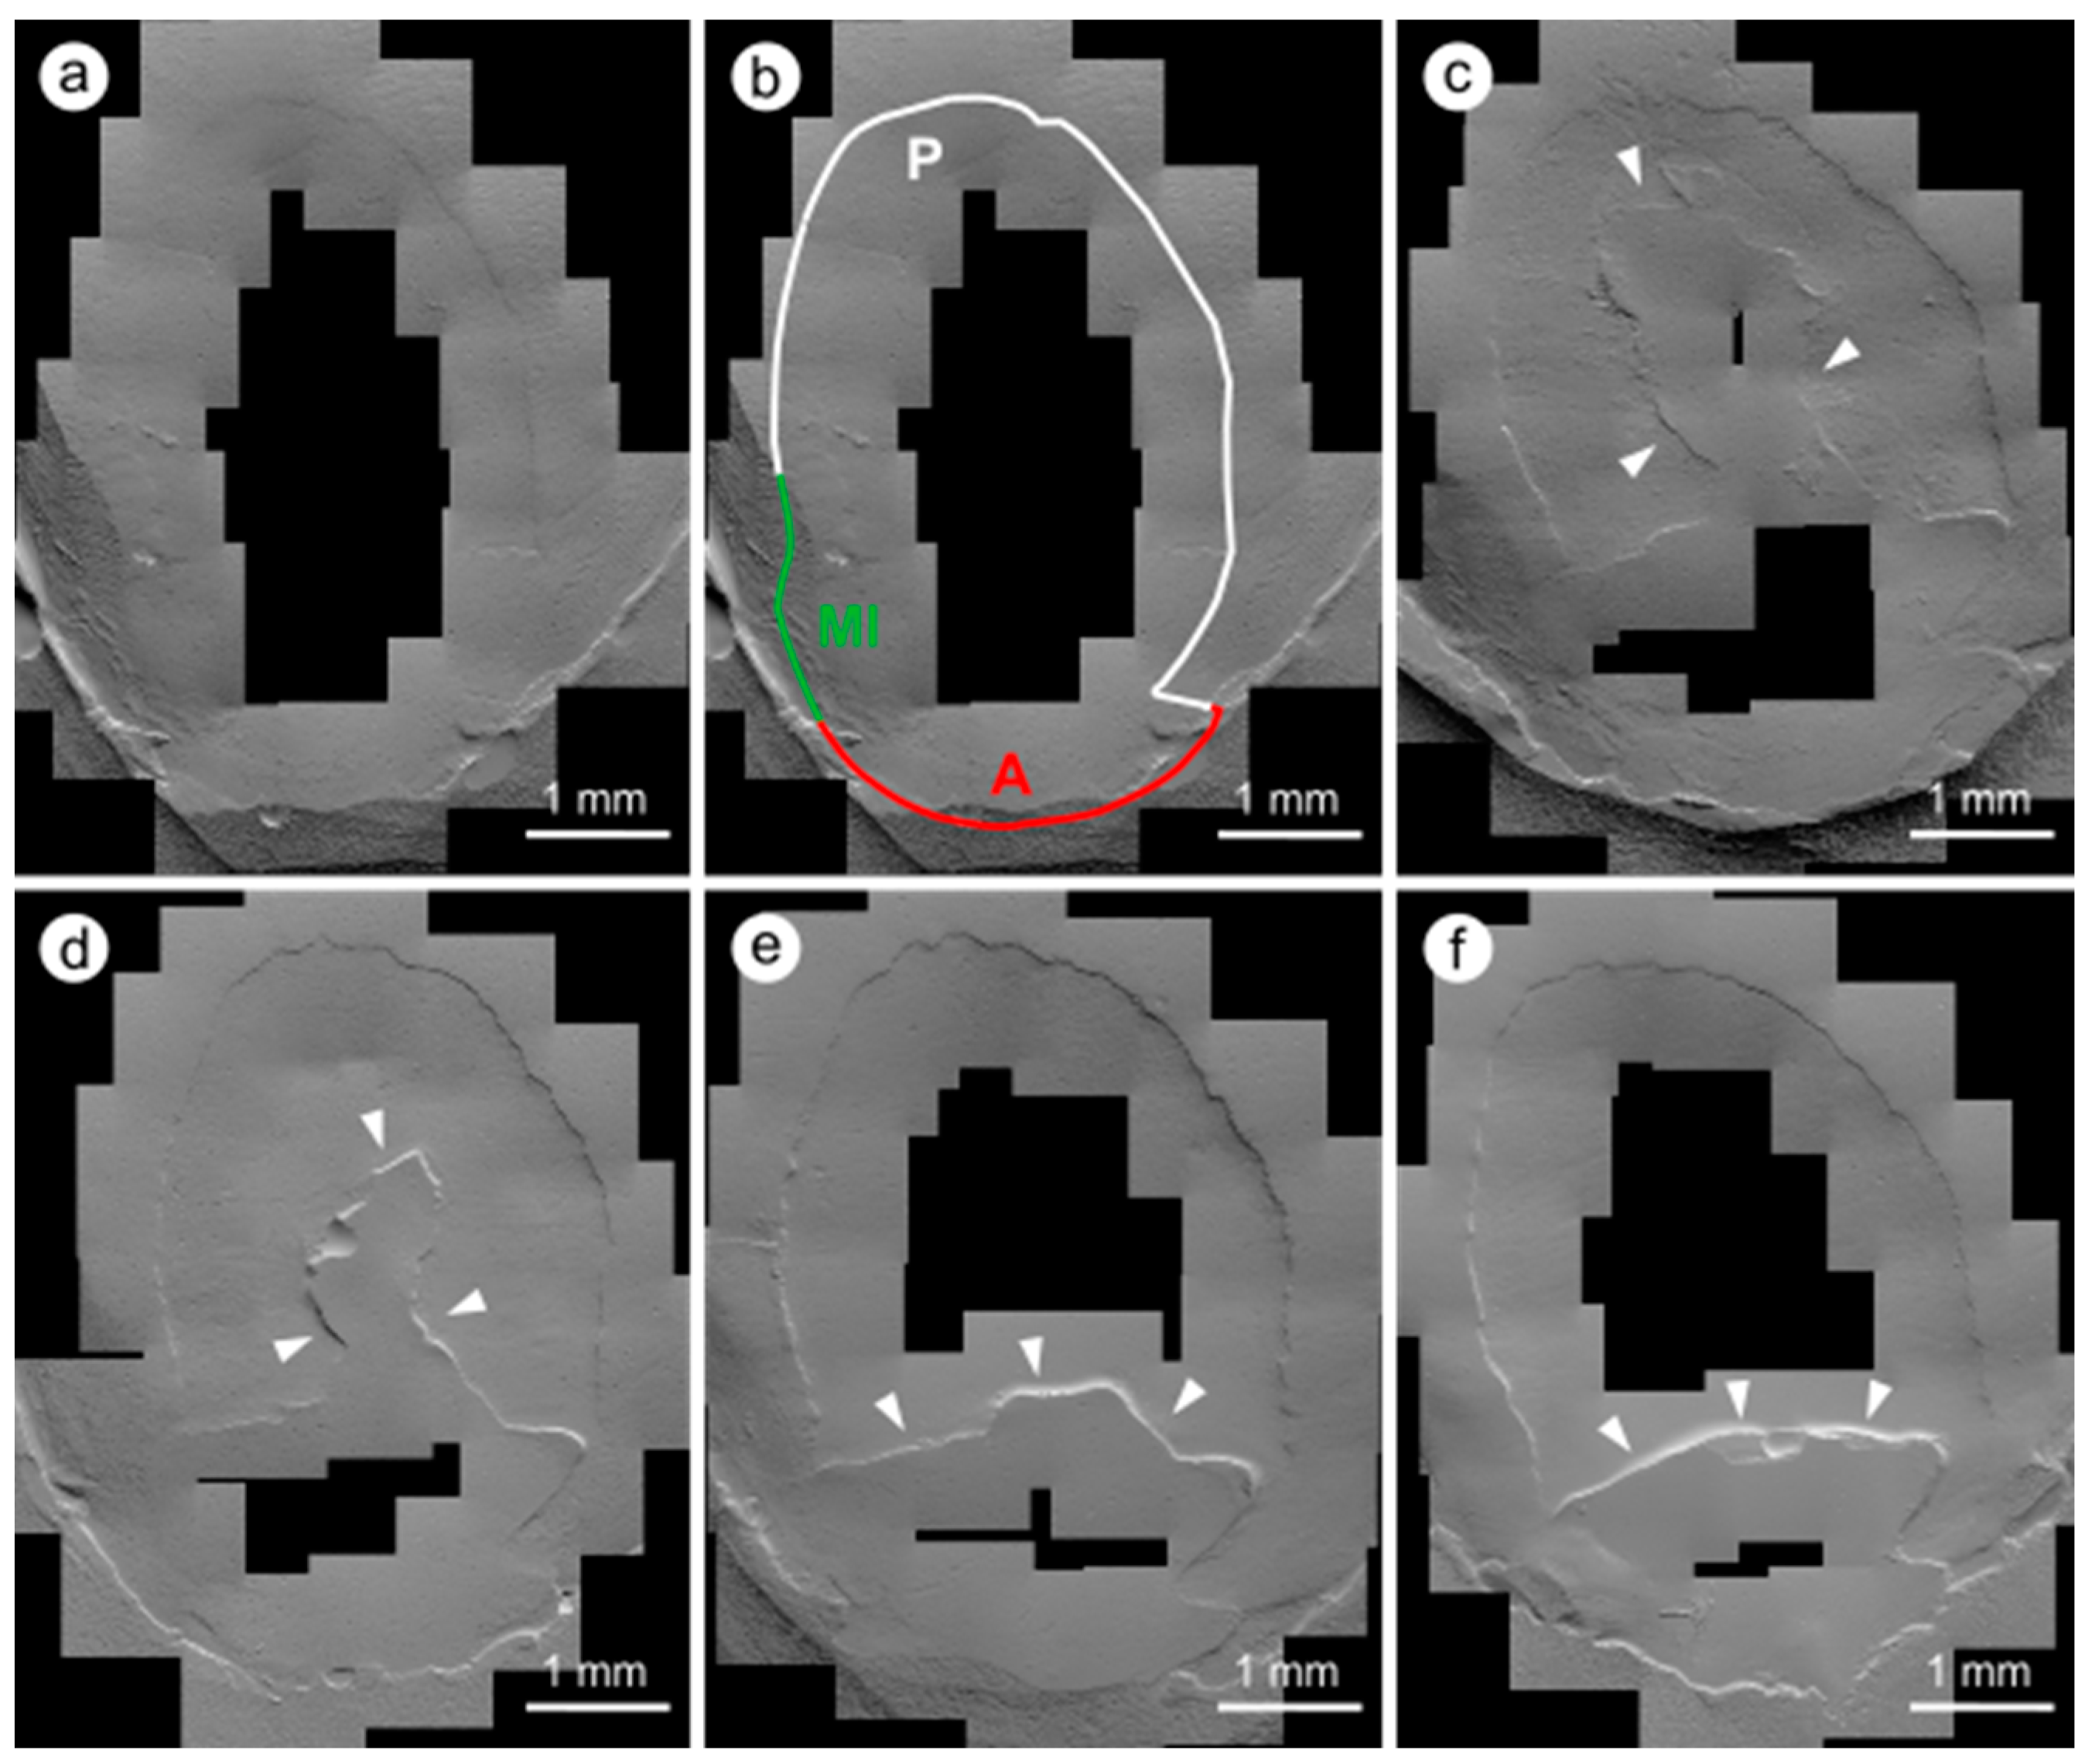

2.5.2. Quantitative Margin Analysis